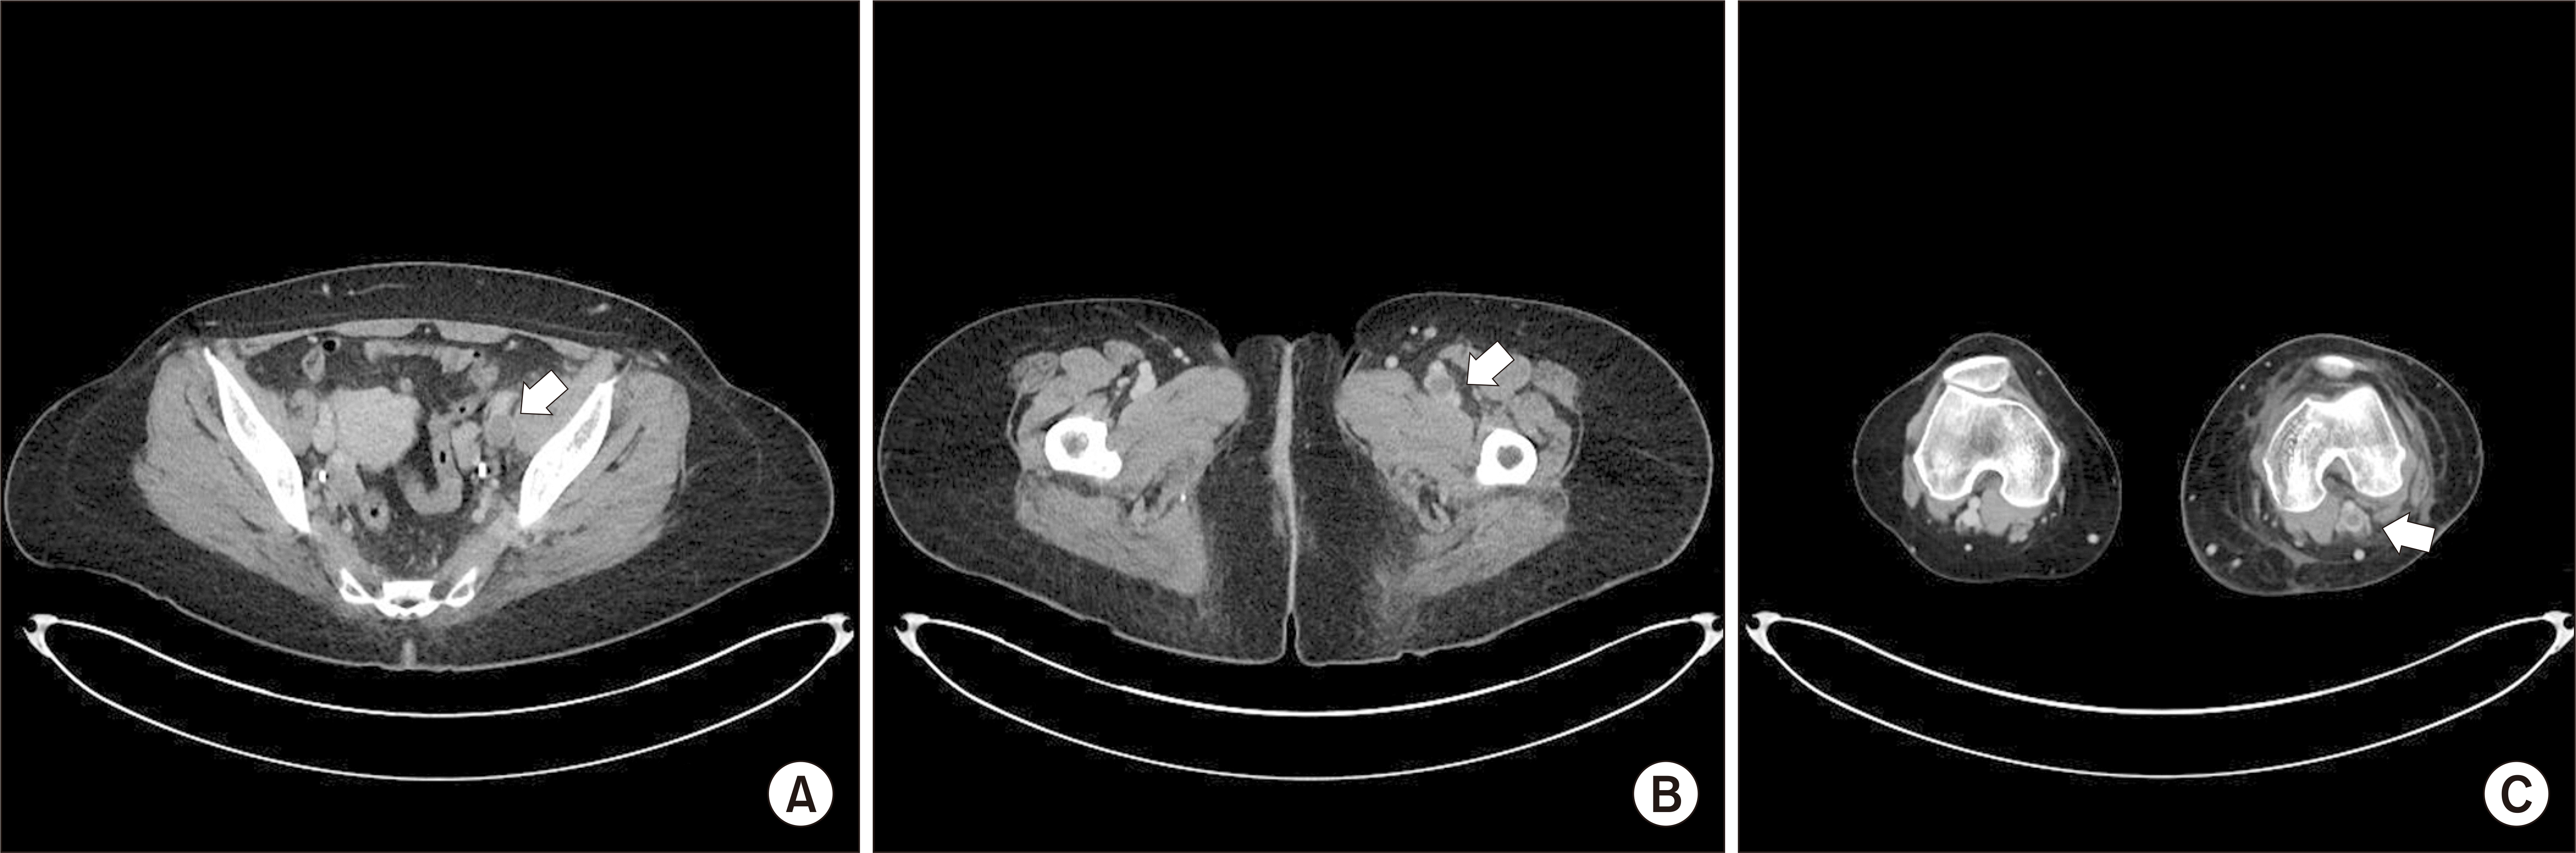

Figure 4

Venous phase in computed tomography angiography shows deep vein thrombosis (arrows) in left common iliac vein (A), femoral vein (B), and popliteal vein (C).